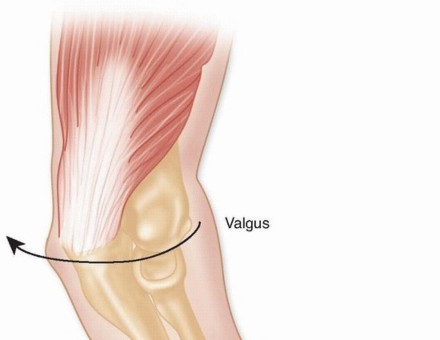

The pathogenesis of elbow fracture-dislocations typically involves high-energy trauma, such as falls from a significant height, motor vehicle collisions, or falls onto an outstretched hand (FOOSH) during sporting activities. The mechanism of injury follows a predictable cascade of soft tissue and osseous failure, classically described by O'Driscoll as the "Circle of Horii." This sequence begins laterally and progresses medially as the forearm is subjected to a combination of axial loading, supination, and valgus stress. As the patient falls, the body rotates internally against the planted hand, applying a supination torque to the forearm that sequentially strips the lateral collateral ligament (LCL) complex, disrupts the anterior and posterior capsule, and finally compromises the medial collateral ligament (MCL).

A profound understanding of elbow anatomy and biomechanics is the bedrock of successful surgical management. The elbow is a highly constrained, modified hinge joint relying on a delicate interplay between primary and secondary stabilizers. The primary stabilizers include the highly congruent ulnohumeral articulation, the anterior bundle of the medial collateral ligament (MCL), and the lateral collateral ligament (LCL) complex. Posterolateral dislocations of the elbow are universally associated with disruption of the LCL and, in severe cases, the MCL. The MCL is the primary stabilizer to valgus stress. It originates from the anteroinferior surface of the medial epicondyle and inserts onto the sublime tubercle at the base of the coronoid.